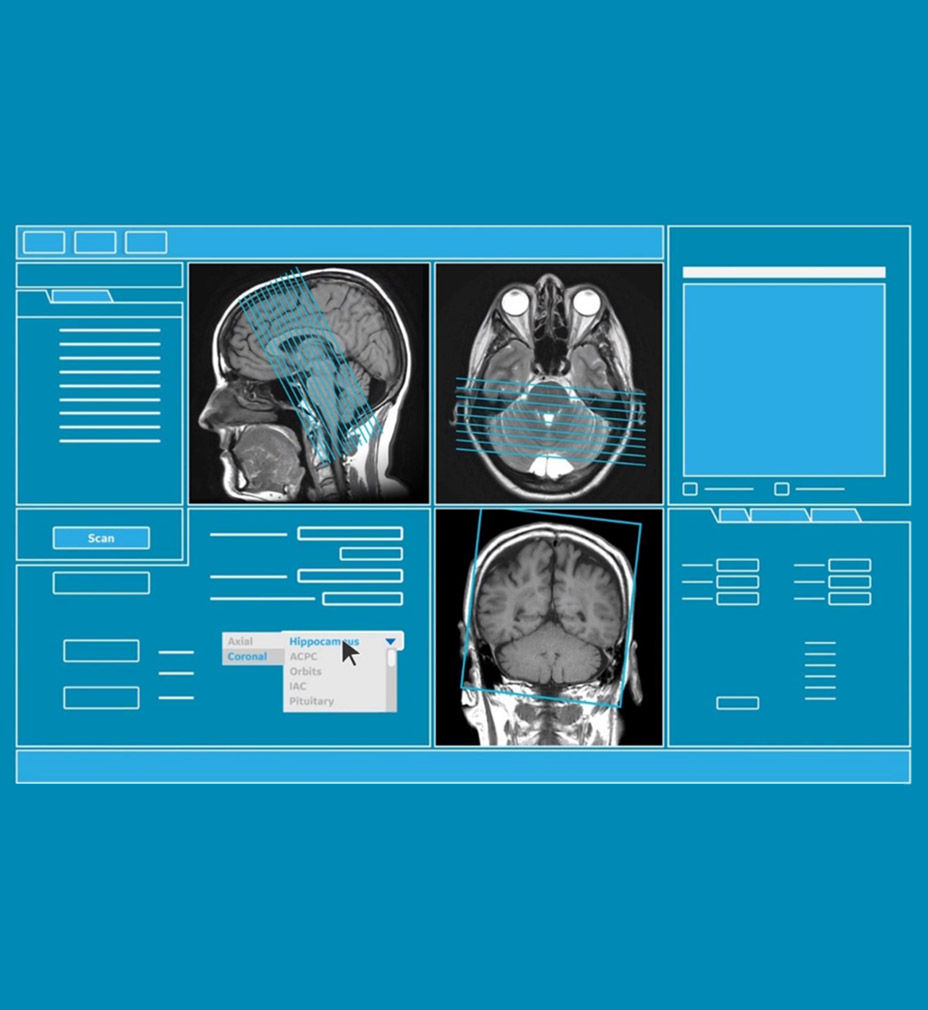

AIR x™ automatically detects patient anatomy and prescribes MRI slices

Eliminate the sources of variation by letting processes flow. AIR x™ uses deep-learning algorithms created from a database of 10's of thousands of images to automatically detect patient anatomy and prescribe MRI slices for routine and challenging neurological and knee exams, delivering consistent and quantifiable results. The automated workflow creates efficiency and reproduces steps used in planning to ensure exam consistency for same patient follow-up.

Determine the best MRI slice placement

AIR x™ automatically detects patient anatomy and prescribes MRI slices for routine and challenging neurological and knee exams, delivering consistent and quantifiable results.